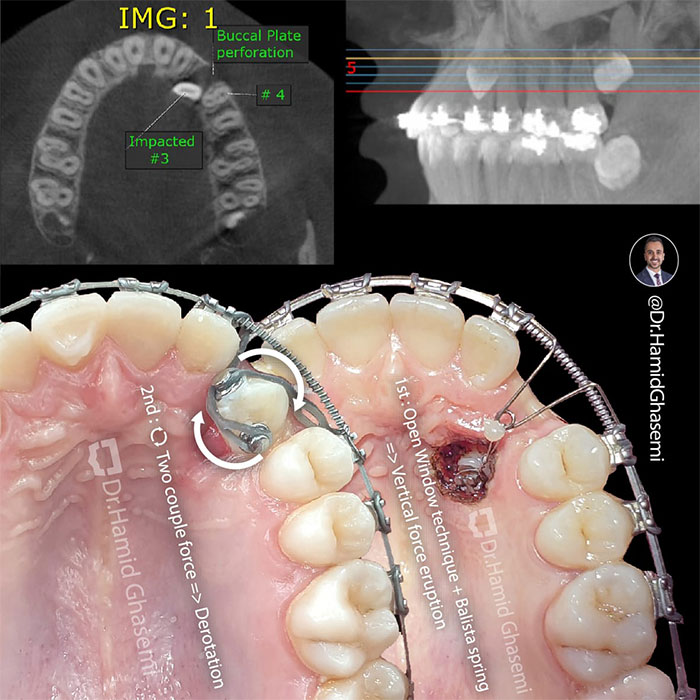

ارتودنسی دندان نهفته؛ راهحلی برای درمان مشکلات پنهان دندانها10 آذر 1403 - 6:20 ب.ظ